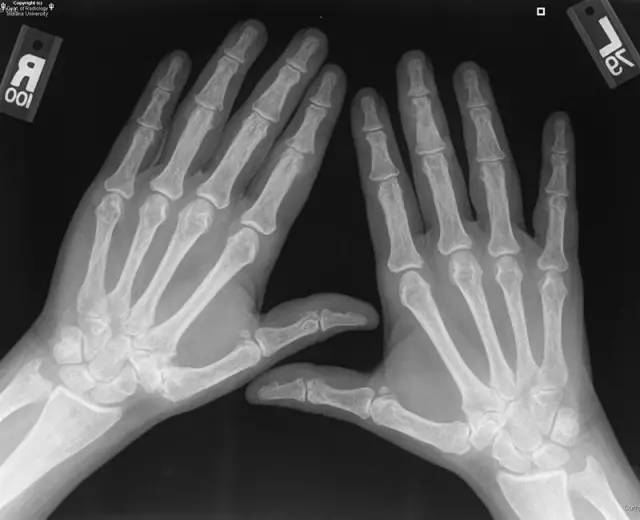

【病例】双手痛风性关节炎1例X线影像表现

【病史】女性,手部疼痛。

【答案】1.B 2.A 3.A 4.B 5.B 6.C

【影像学表现】双手近侧、远侧多发指间关节附近骨质侵蚀。

【诊断】痛风Gout